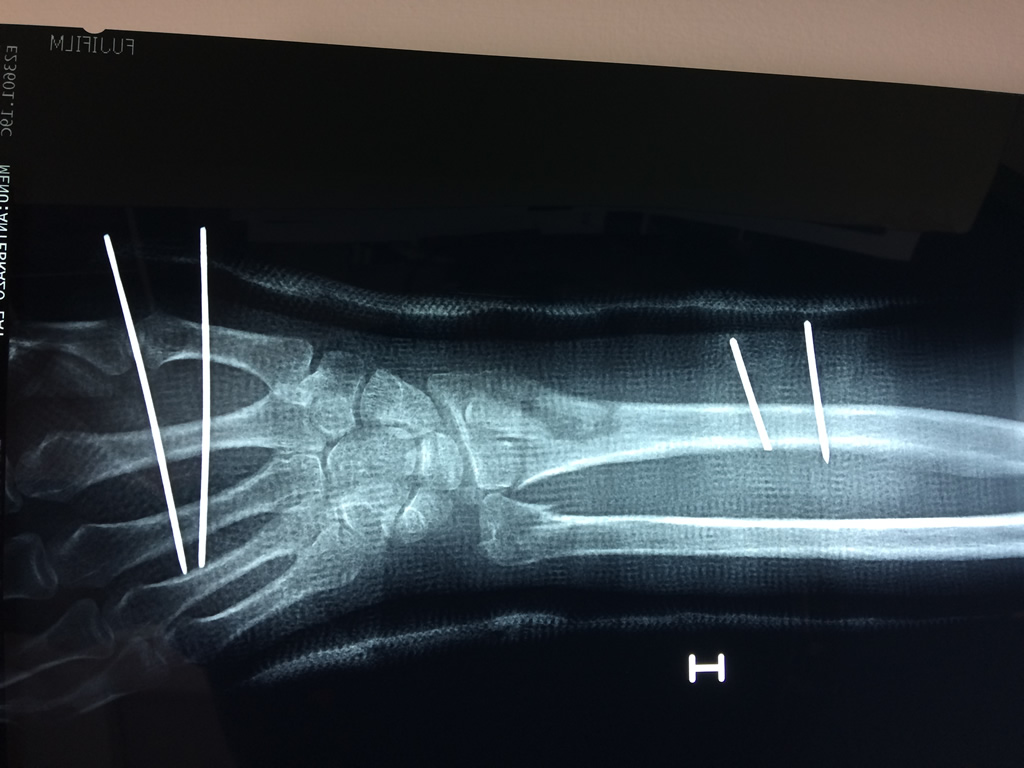

Los procedimientos más comunes en cirugía de la mano son aquellos destinados a reparar traumatismos, incluyendo lesiones de tendones, nervios, vasos sanguíneos, y articulaciones; huesos fracturados; y quemaduras, cortes, y otros daños de la piel.